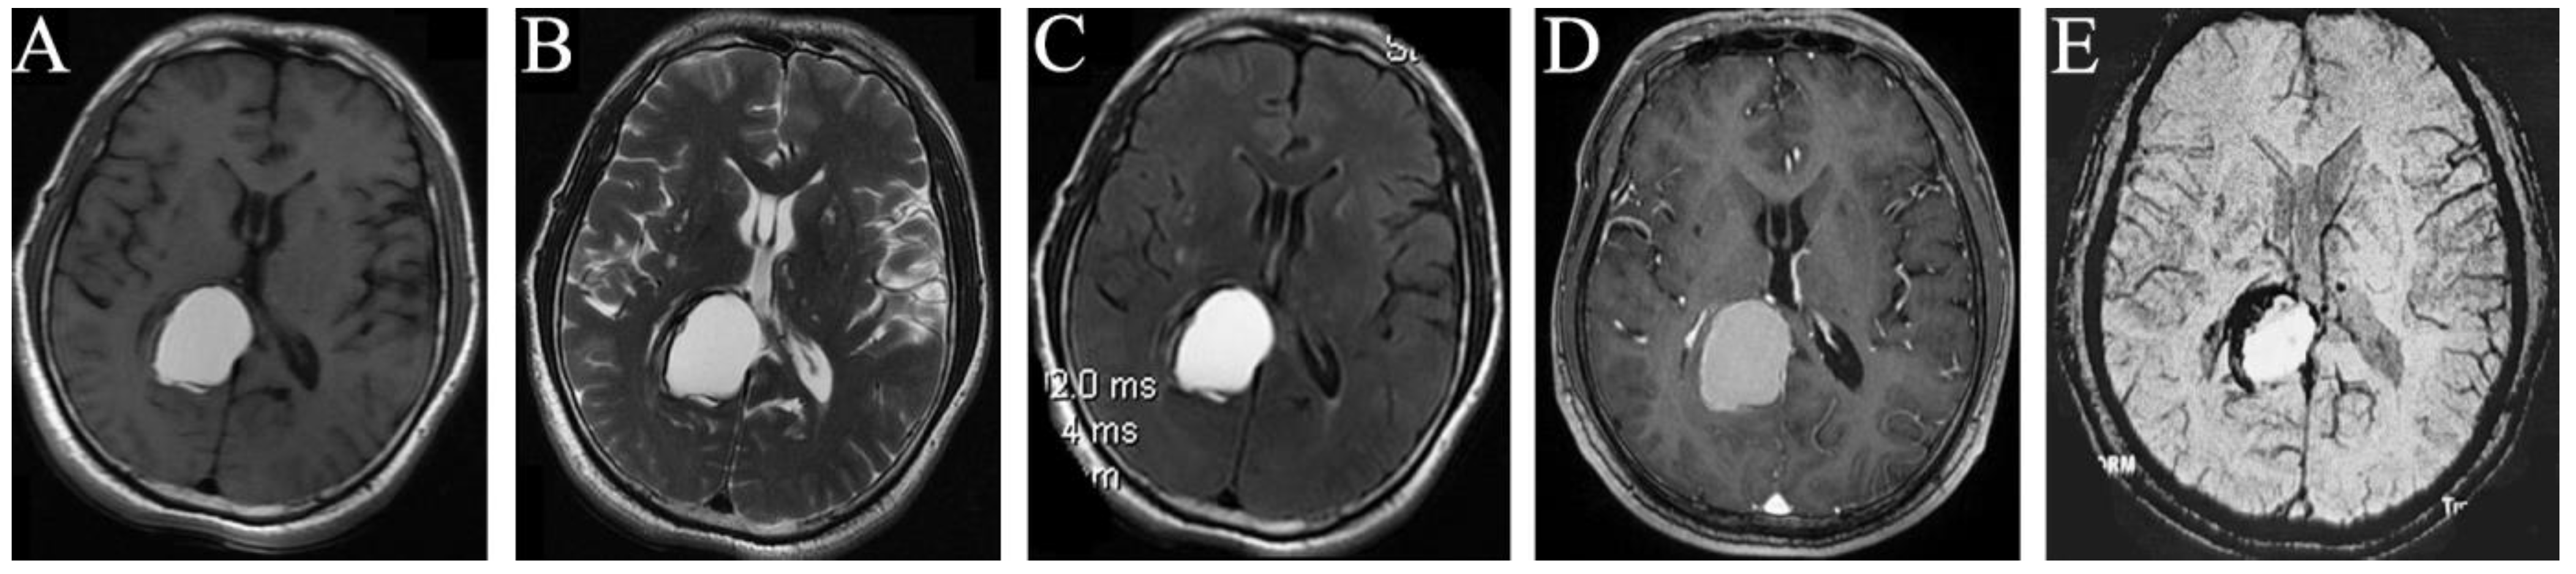

Figure 2.

MRI manifestations of the space-occupying intracranial fungal lesion on 9 July 2020. T1WI (A), T2WI (B), T2 Flair (C), and Contrast-enhanced T1 (D) show that the right occipital lobe occupation became obviously larger than before, with predominantly high signals on T1WI (A), T2WI (B), and T2 Flair (C), and equally enhanced signal on Contrast-enhanced T1 (D); SWI examination found no vascular diseases (E).

Imaging examination: the intracranial MRI revealed a space-occupying lesion with a regular shape and clear boundary in the right occipital lobe. Further, the corpus callosum and posterior horn of the right lateral ventricle were compressed. The occupation was 2.8 × 1.7 and 4.0 × 2.6 cm2 in size at the maximum imaging level on 21 October 2015 (Figure 1A–E) and 9 July 2020 (Figure 2A–E), respectively, with annular low signal shadow in the edge and small edema signal in the surrounding area, showing a high signal in the T2-weighted and T2 flair image and an equally high signal in the contrast-enhanced T1 image (Figure 1A–D and Figure 2A–D). The T1-weighted image of this occupation first revealed an equally low signal, and after the occupation became larger, it demonstrated a high signal (Figure 1A and Figure 2A). Moreover, the susceptibility-weighted imaging (SWI) examination found no vascular diseases (Figure 2E), and the CT revealed a low density of this occupation (Figure 1E).